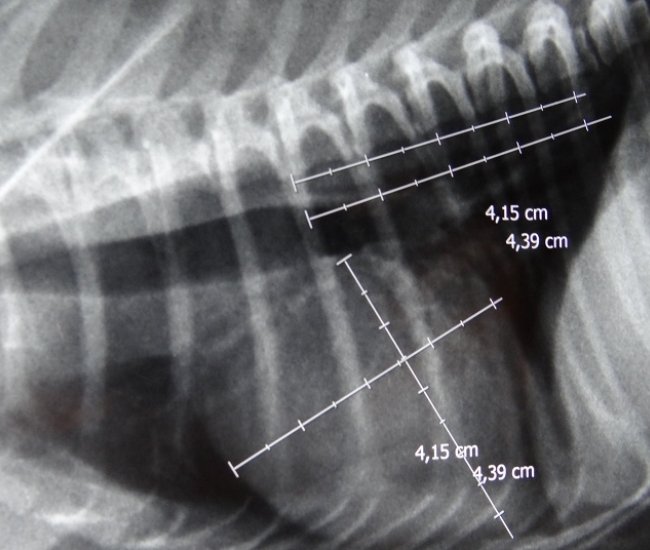

- Diferentemente do raio-x analógico, este raio-x oferece altíssima definição e todas as vantagens da tecnologia digital. É possível aproximar a imagem, trabalhar o contraste, exposição.O software permite ainda avaliações da medida cardíaca do animal e graus de displasia coxofemoral, por exemplo – explica o Dr. Nardeli Lucena.

- sofware com medidas para avaliações do tamanho cardíaco e medições dos ângulos de Norberg para diagnóstico e classificação de displasias coxofemorais;